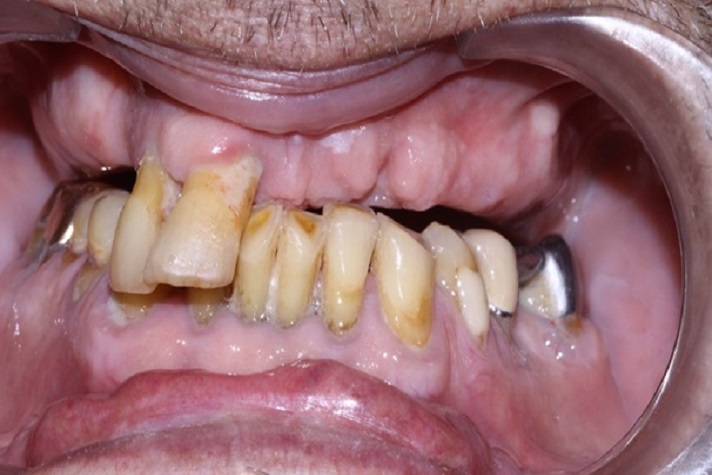

Tall and Tilted Pin Hole Immediate Loading ( TTPHIL) is a modern and most reliable technique for dental implantation. The special feature of such method is that dentist combine long and wide implants with bi-cortical support bone.

The All on 6 and All on 4 technique apply that method of implants placement.

This technique also use immediate loading so the implants are placed right after teeth extraction.

This case report show the successful All on 6 dental implantation using Alpha Dent implants.